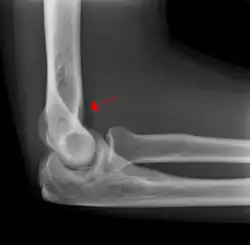

In children, a posterior fat pad sign suggests a condylar fracture of the humerus. In adults it suggests a radial head fracture.

The posterior fat pad is normally pressed in the olecranon fossa by the triceps tendon, and hence invisible on lateral radiograph of the elbow.[3] When there is a fracture of the distal humerus, or other pathology involving the elbow joint, inflammation develops around the synovial membrane forcing the fat pad out of its normal physiologic resting place. This is visible as the "posterior fat pad sign" and is often the only visible marker of a fracture, particularly in the pediatrics population.